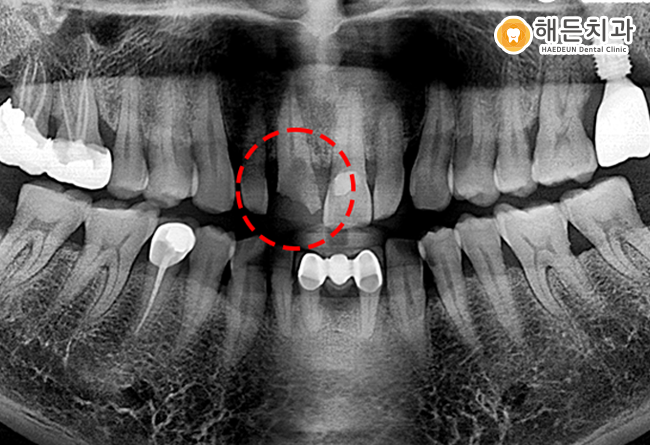

위의 환자분의 경우 과거 작은 앞니에 신경치료 및 크라운 치료를 받으셨는데요.

하지만 신경치료를 진행했음에도 불구하고 염증이 재발하여 임플란트를 식립해야 하는 사례도 많이 있습니다.

위의 환자분의 경우 보시다시피 착색도 많으며 구강관리가 전혀 되지 않았습니다.

이로 인해 신경치료 한 치아라도 염증이 재발하였으며, 흔들림이 나타나 임플란트를 진행하게 되었는데요.

잇몸 염증으로 인해 치조골이 녹아 뼈이식을 진행하고 임플란트를 식립을 진행하게 되었습니다.